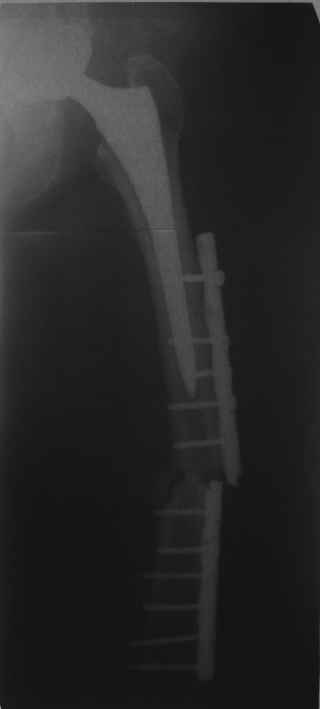

Re: Перипротезный перелом

Уважаемый, Александр Николаевич! Здравствуйте,подскажите пожалуйста, где можно подробнее ознакомиться с описанием конструкции штифта, который был использован в вышеуказанном клиническом случае. Имеем похожую ситуацию: закрытый перелом в средней трети диафиза бедренной кости на сломанной пластине и эндопротез тазобедренного сустава. Думаем,о реостеосинтезе пластиной LCP, будет ли уместен дистальный бедренный гвоздь описанный выше?! Спасибо.

Это сплошной титановый стержень. На дистальном конце отверстия под кондуктор. На другом - канал под ножку глубиной 60 мм, стенки толщиной 2,5-3 мм. И там же продольный пропил, чтобы канал мог адаптироваться к ножке.

Обещанные ранее снимки Заранее спасибо.